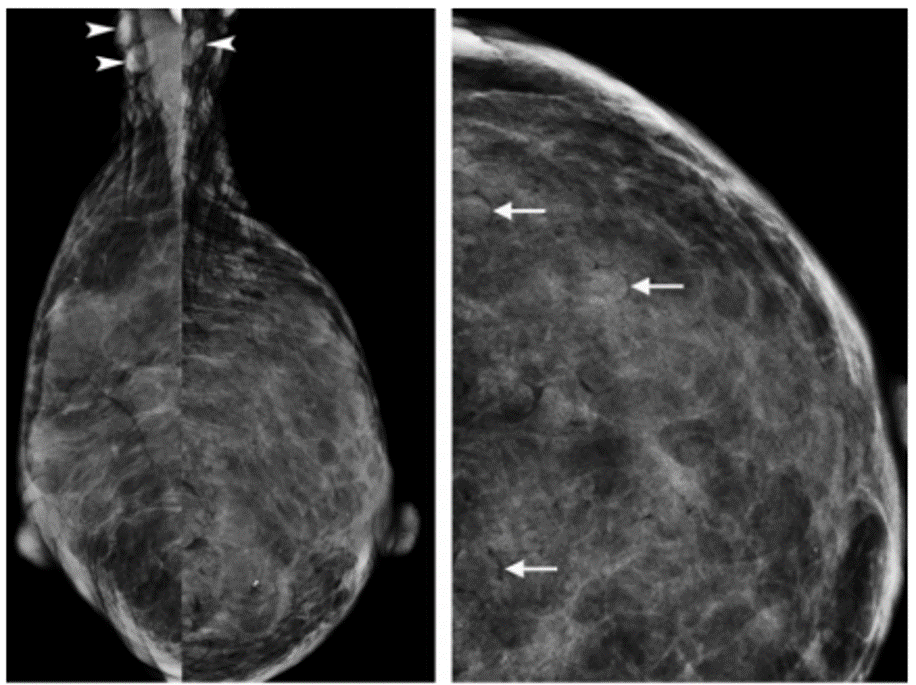

What clinical history most likely accounts for the imaging findings shown?

Bilateral reduction mammoplasty

NF-1 in an 80-yearold woman with multiple superficial neurofibromas over her torso. Right and left MLO mammograms (a) and left craniocaudal mammogram (b) show numerous dense, circumscribed ovoid masses surrounded by lucent halos of air in the axillae (arrowheads in a) and breasts (arrows in b), findings that represent cutaneous neurofibromas.